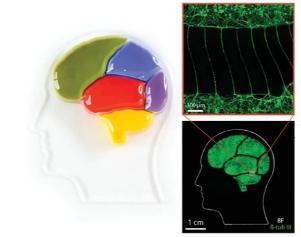

3D打印軟光刻法制備復雜分區(qū)微流體神經(jīng)裝置,為帕金森病的體外研究提供了平臺

瑞典隆德大學JankoKajtez博士及其團隊提出了一種混合添加劑制造方法,用于制造開放式、分隔有序的微流體神經(jīng)裝置。該方法具有更高的裝置設計自由度,避免了手動后處理的需要,同時提高了系統(tǒng)的生物相容性。

圖1.3D打印的軟光刻技術,用于復雜的分區(qū)微流體神經(jīng)裝置

圖3.具有復雜設計的制造設備:a)圖像顯示了包含用于三種設備設計的母模的硅片:“大腦”設備,同心圓設備和軸切術設備。每種設計的一種設備都經(jīng)過完全3D打印,而其他模具則留空,以便可視化與最終產(chǎn)品相比的起點。b)制成的設備的照片。將彩色墨水倒入每個隔室中,以證明各個隔室之間的物理分離。c)隔室壁橫截面的反明場圖像。尺寸線的藍色部分表示壁上印有墊片墨水的部分。紅色部分表示墻上印有隔室墨水的肋狀部分。d)隔室壁底面上的圖案化波浪形微通道的明場圖像。β-微管蛋白III,一種微管元件,幾乎只存在于神經(jīng)元中;左:隔室中間神經(jīng)元的高倍熒光圖像;右:通過微通道延伸投影的神經(jīng)元的高倍熒光圖像。

近日,瑞典隆德大學JankoKajtez博士及其團隊開發(fā)了一種新型的用于制造微流體裝置的增材制造技術,并將其命名為3D打印軟光刻法。該方法在保留了傳統(tǒng)軟光刻法的優(yōu)點的同時,最小化了設備的手動后處理,增加了設計可能性,簡化了高縱橫比特征的制造,并且可以通過控制彈性體的沉積減少PDMS的含量。此外,3D打印軟光刻法能夠?qū)崿F(xiàn)跨尺度特性精確的快速成型,以及實現(xiàn)了將新材料引入軟光刻法的可能性。為了驗證這種新制造方法的潛力,作者利用快速成型方法進行微觀結構設計,來制造人類神經(jīng)干細胞模擬黑質(zhì)紋狀體通路,并通過此設計最大限度地增加了中腦腹及前腦背兩個室間多巴胺能投射物的單向生長。

該裝置不僅為帕金森病(PD)的體外研究提供了平臺,更展示了3D打印軟光刻法在神經(jīng)科學中的通用性。